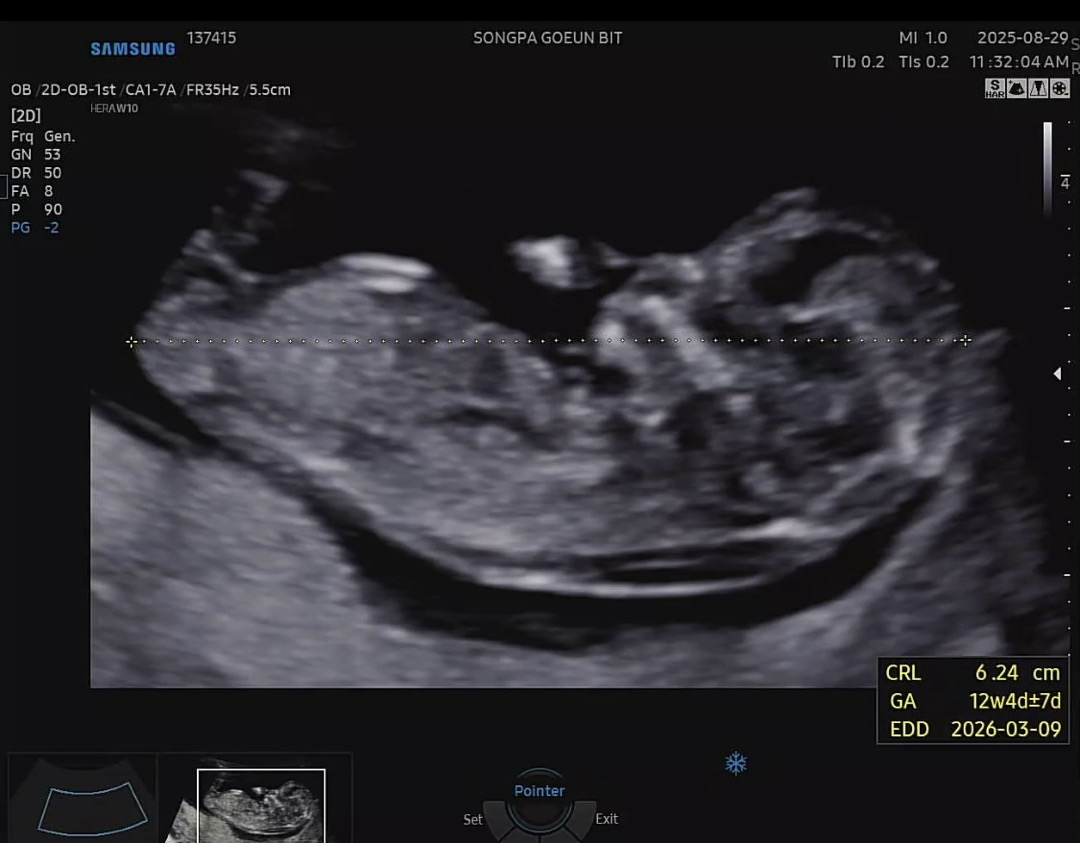

12주 각도법 봐주세요

제가 봤을땐 아들같은데.. 마구 마구 투표해주세욤🩵🩵🩵